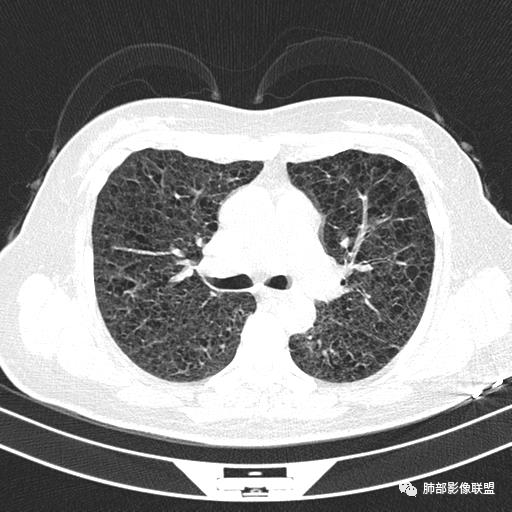

双肺弥漫囊腔,累及肋膈角,囊腔形态相对规则单一。

CT平扫示双肺弥漫分布大小不等囊状薄壁透光区,无内、中、外带分布差异,间质稍示增厚。拟LAM

中年女性育龄期妇女,咳嗽气喘,无吸烟史,有苯吸入史。影像:双肺弥漫均匀小囊腔,无明显分布优势,囊腔形态欠规则,壁薄,部分囊腔边缘血管征,伴双肺弥漫磨玻璃影,无结节,考虑lam,鉴别苯中毒肺损伤,囊腔多有分布优势,小叶中心分布为主,形态规整等

女,46,活动性气喘1年。苯吸入史半年。胸部CT:两肺弥漫囊腔,上至肺尖,下至肋膈角,形态类似小囊腔。考虑:LAM,鉴别LIP,BHD,PLCH等。

双肺弥漫大小不一薄壁含气囊腔,囊间肺组织正常,正常肺背景,肺尖肺底受累;青年女性,气喘,支持LAM

CT表现:双肺弥漫大小不等的薄壁囊腔,囊壁<2mm,外形规则,血管影多位于囊腔周围,囊腔之间肺组织正常,随着疾病进展到晚期,囊腔变大、增多,不可胜数,囊腔可融合成较大的囊,与肺气肿相似,形成间质性肺纤维化。部分病例可出现结节影。